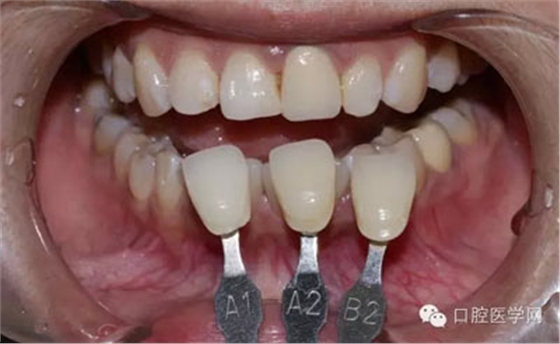

1、術(shù)前比色照

將比色照飽和度調(diào)到最低有助于牙齒明度的選擇

將比色照的飽和度調(diào)到最高有助于牙齒道飽和度選擇